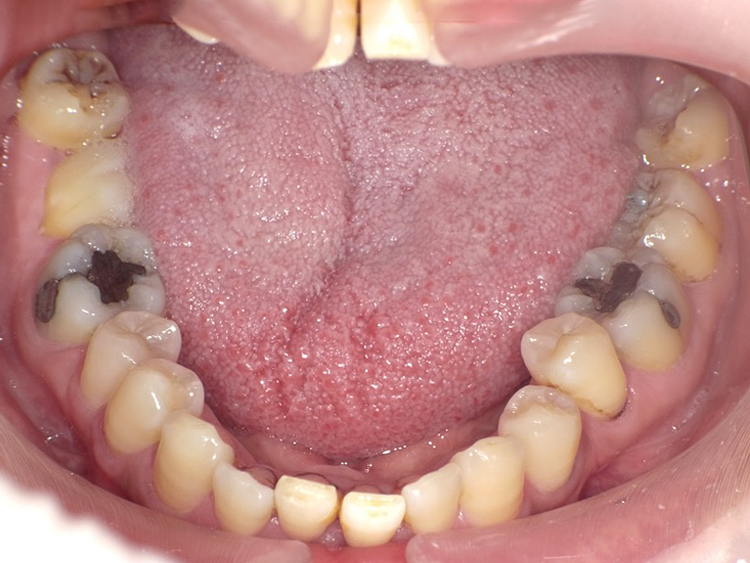

症例4

Before

After

| 主訴 | 上下前歯のがたつき |

|---|---|

| 年齢 | --- |

| 治療 期間 |

約9ヶ月 |

| 治療 内容 |

インビザラインiGoで上下顎の治療。 |

| 治療費 | ¥550,000(税込)/調整料含む |

| 治療のリスク | 矯正終了後は、リテーナーを指示通りに使用し、歯の後戻りを防ぐ必要があります。 |